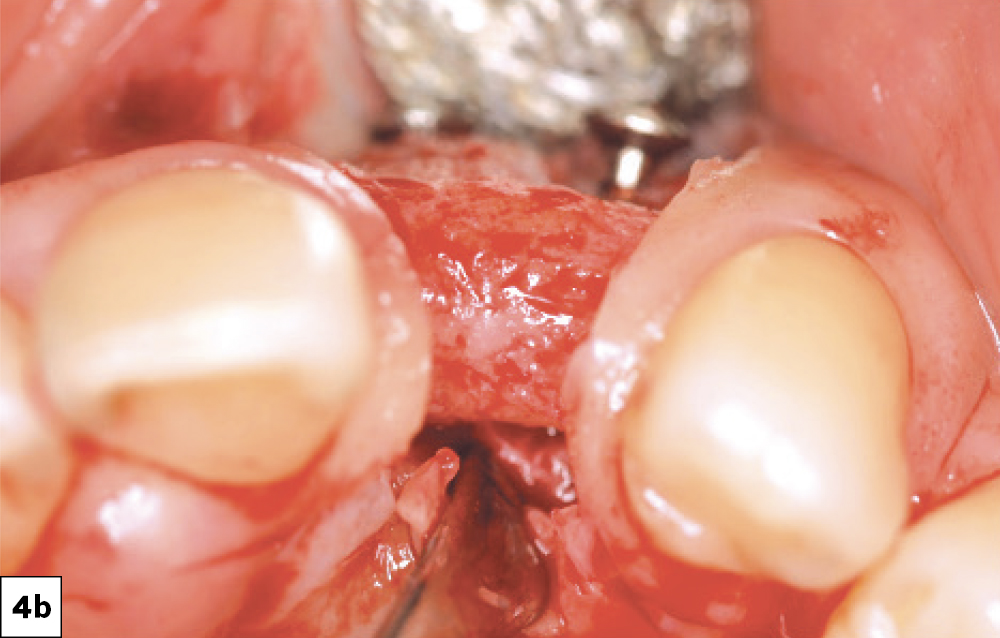

When incisions are made near adjacent natural teeth, “papilla-sparing” incisions should be incorporated. These incisions are designed to allow for 1.0 to 1.5 mm of the interproximal papilla adjacent to each tooth to remain, thereby minimizing tissue recession. The purpose of this incision design is to ensure primary closure with no voids and minimal scarring, promoting optimal healing and maintaining the integrity of the interproximal tissues (Figs. 4a, 4b).

Papilla-sparing incision leaving about 1 mm of papillary tissue adjacent to the natural tooth.

Figures 4a, 4b: Papilla-sparing incision leaving about 1 mm of papillary tissue adjacent to the natural tooth.